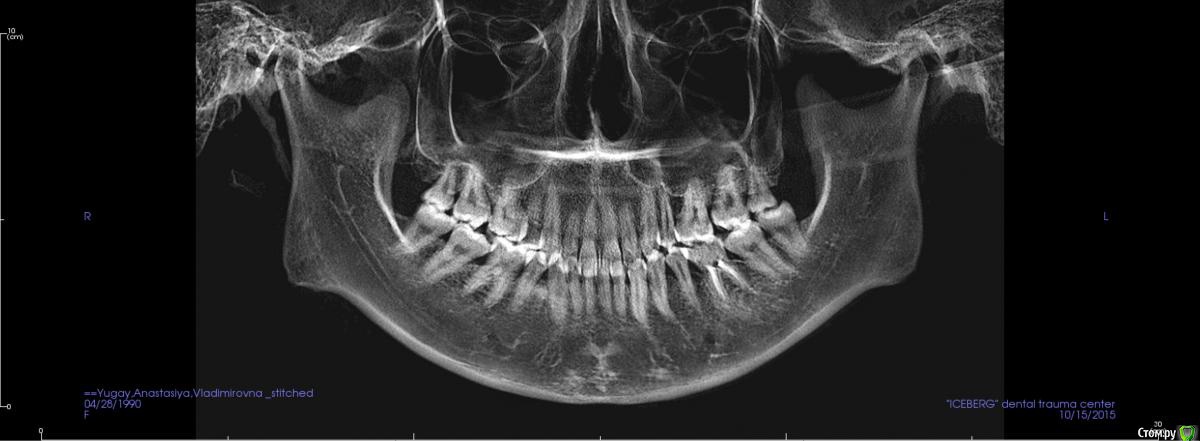

Головные боли, артроз ВНЧС, дистальный глубокий прикус, удалены 4ки на вч и 5 на нч

Сейчас мне 25 лет. С детства был дистальный глубокий прикус, зубы на верхней челюсти выпирали вперед, на нижней челюсти присутствовала скученность, из-за чего была удалена "мешающая" 5ка. Вероятно, этот зуб стоило сохранить.

В 2007-2008 гг. проходила ортодонтическое лечение с удалением 4ок на верхней челюсти. Резцовые зубы были перемещены назад, эстетически результат был удовлетворительным. Однако, проблема неправильного прикуса решена не была.

То, что эти боли могут быть следствием проблем с ВНЧС, узнала в последнюю очередь. МРТ показало, что у меня артроз суставов - 3 степени слева, полная вентрально-латерация дислокация суставного диска без репозиции; 1 степени справа, с репозицией, гипермобильность правого сустава. Асимметрии лица нет, однако рот открывается по S-образной траектории (почти не заметно), при широком открывании рта очень редко слышен щелчок, хрустов нет, слегка выпирает правый сустав. Заключение по МРТ с подробным описанием в приложении.

Заключение по МРТ, ОПТГ, цефалограмма в боковой проекции (справа и слева) и фото зубов - в приложении.

Все снимки по результатам КЛКТ (5 мб) можно скачать по ссылке https://www.dropbox.com/s/4c026r3ewd8zz0l/KLKT.zip?dl=0